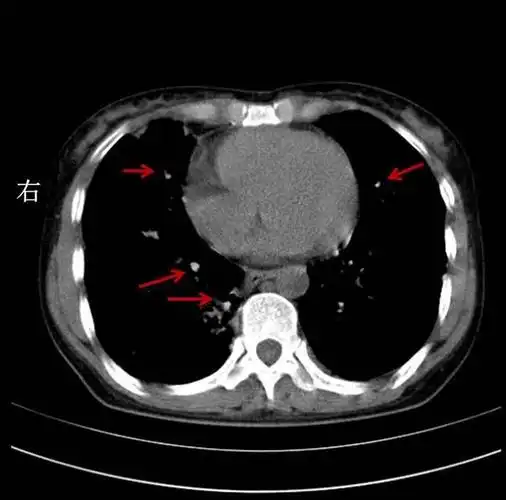

双肺可见多个纤维空洞,条索状,斑点状影,病灶有钙化.

右肺纤维化病灶图片

双肺纤维化病灶,说明病史很长.斑片状影,说明是活动性病灶.